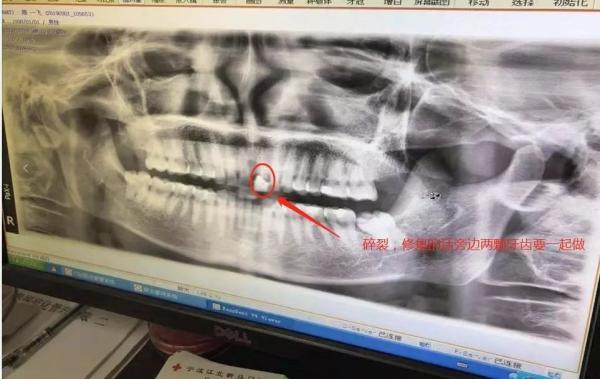

看到这个情况,健身房的工作人员马上上前查看,并且和陈先生一起去医院进行了检查口腔招聘网免费发布口腔招聘信息,。而据陈先生提供的医院相关证明显示,其上颚一颗门牙碎裂,需要和旁边两颗牙齿一起进行修复,鼻梁也有轻微的损伤牙科医生免费找工作,。初步估计治疗费用在10000多元口腔修复医生,口腔种植医生,